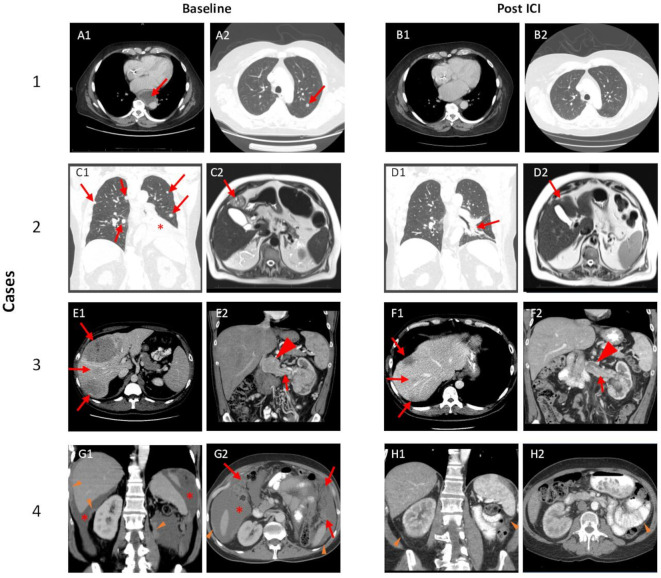

Figure 2.

ICI-associated tumor changes. Case 1: Red arrows highlight representative lesions at baseline including a paraesophageal lymph node, which was biopsied (A1) and pulmonary nodule (A2). Post-ICI imaging (B1 and B2) demonstrate resolution of these lesions. Case 2: Red arrows show representative pulmonary (C1) and hepatic lesions (C2); red asterisk highlights left lower lobe consolidation/atelectasis secondary to metastatic lesion and pleural effusion (C1). Post-ICI imaging demonstrates substantial improvement of pulmonary disease (D1) and the liver lesion (D2). Case 3: Red arrows show large liver masses (E1) and tumor thrombus (E2) with mass-like enlargement of tumor thrombus at the confluence with the inferior vena cava (arrowhead). Post-ICI imaging shows significant shrinkage of liver metastases (F1) and tumor thrombus (F2). Case 4: Baseline imaging with peritoneal deposits (orange arrowheads), malignant ascites (red asterisk) (G1), and omental caking (red arrows) (G2). Post-ICI imaging demonstrates resolution of ascites and omental caking, as well as significant reduction in peritoneal deposits (orange arrowheads). ICI, immune checkpoint inhibitor.